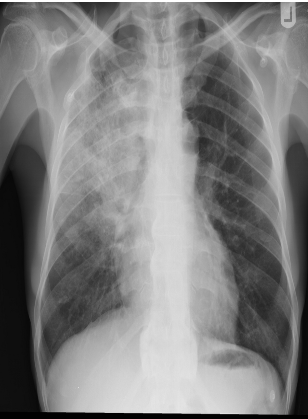

- CXR:

- The appearance of consolidation on CXR is reliable for the diagnosis of pneumonia, but CXR appearances are not reliable for distinguishing between viral and bacterial infection as there is considerable overlap.

- The CXR may appear normal early in the disease. However, as an approximate guide:

- Bacterial pneumonia:

- Lobar consolidation (air bronchogram) occasionally with parapneumonic effusion. Pneumatocoele and abscesses suggest staphylococcal pneumonia

Chest X-Ray showing patch of pneumonia

These chest X rays compare clear, healthy lungs with the cloudy, inflamed lung tissue of pneumonia.

Right lower lobe consolidation in a patient with bacterial pneumonia.